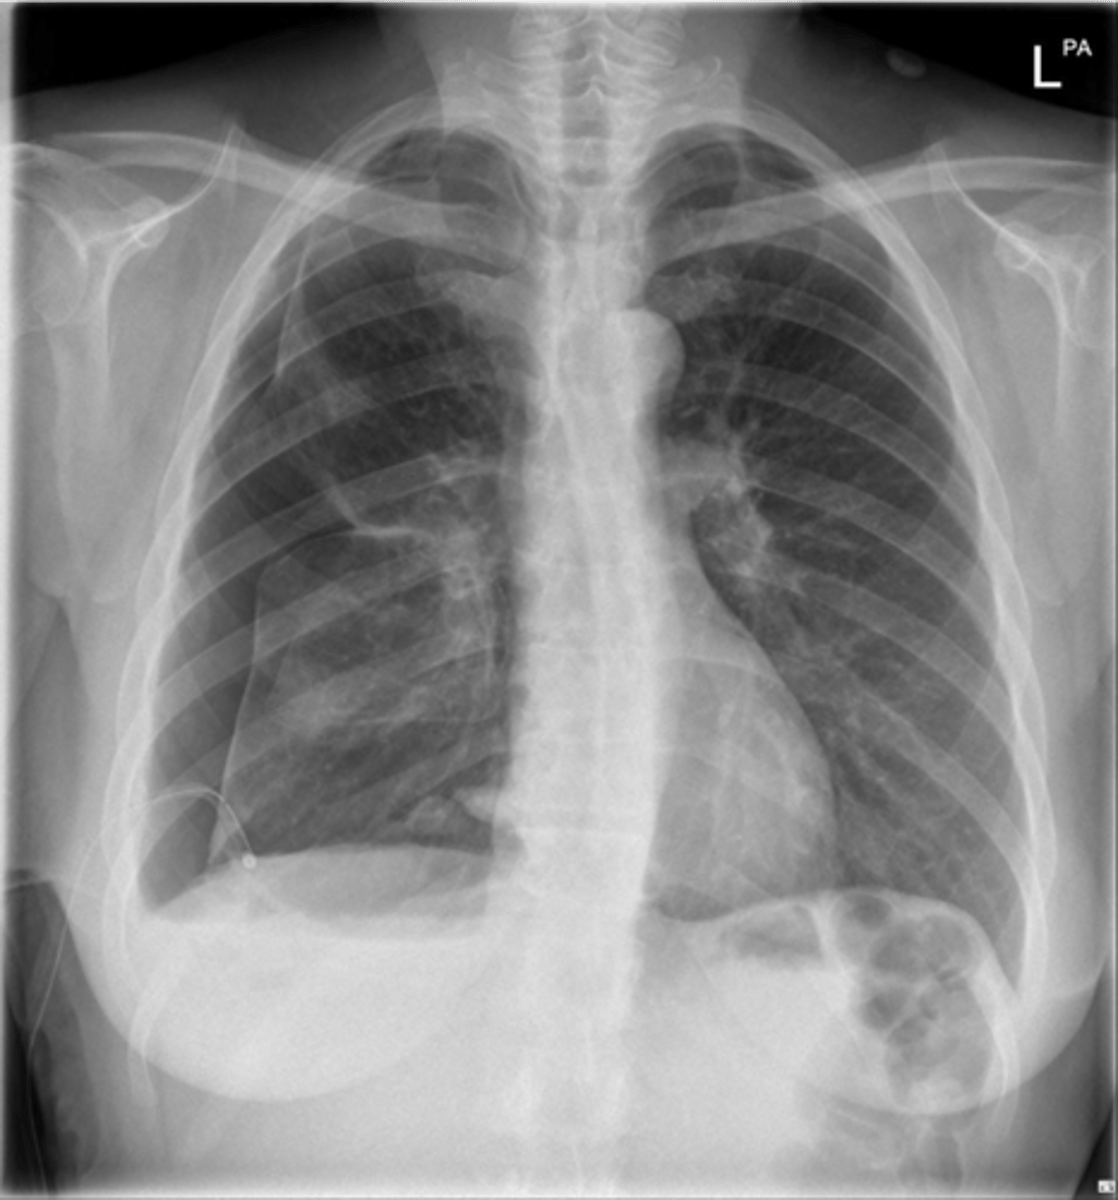

Pneumomediastinum (mediastinal emphysema)

Pneumomediastinum

Pleural effusion

Pleural effusion

Pleural effusion (right sided)

congestive heart failure

congestive heart failure